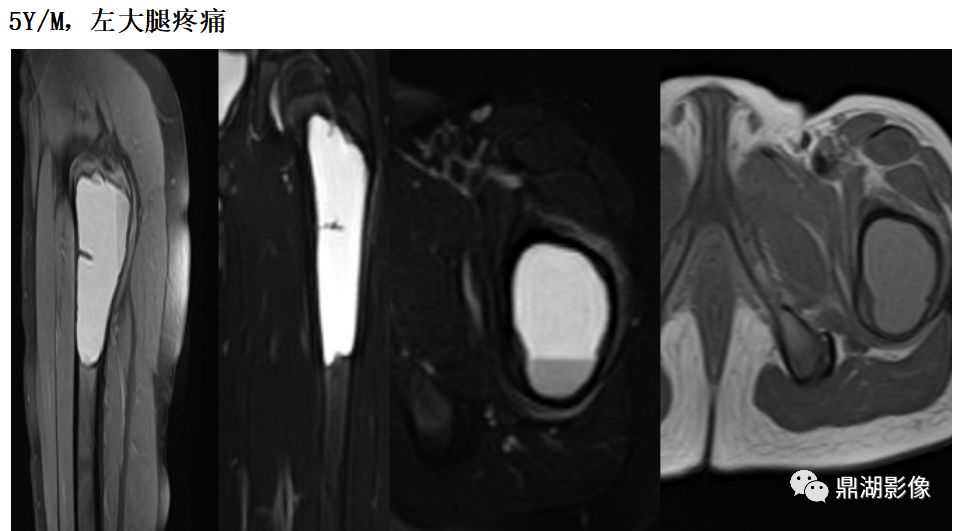

动脉瘤样骨囊肿

好发于股骨上端、椎体和附件

多发生于10-20岁青少年

囊状膨胀性骨破坏,可见骨性分隔,无钙化

局部骨皮质变薄,骨骼膨大

增强扫描明显强化,可见有粗大的供血动脉

液-液平面为MR特征表现,T2WI上其上部以液体为主,呈现高信号,而下部以含铁血黄素为主,为低信号